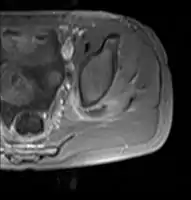

Transverse T2 magnetic resonance imaging section through the hip region showing abscess collection in a patient with pyomyositis.

Diagnostic methodDiagnostic method used for PM includes ultrasound, CT scan and MRI. Ultrasound can be helpful in showing muscular heterogeneity or a purulent collection but it is not useful during the first stage of the disease. CT scan can confirm the diagnosis before abscesses occur with enlargement of the involved muscles and hypodensity when abscess is present, terogenous attenuation and fluid collection with rim enhancement can be found. MRI is useful to assess PM and determine its localization and extension